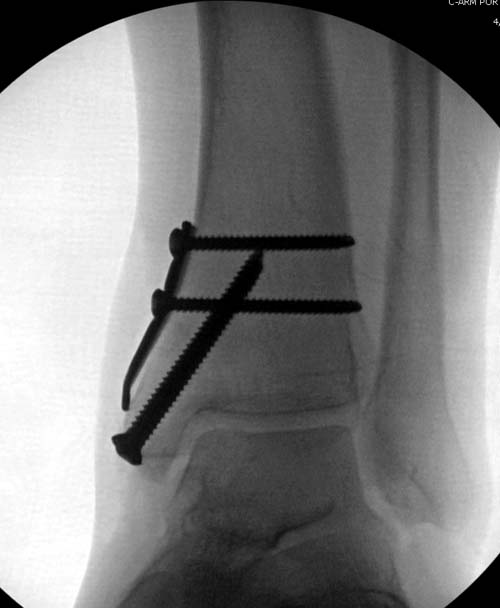

Артроскопия с дебридментом приносит облегчение, но огромные медиально-верхние дефекты надо замещать. Хирургический доступ через медиальную лодыжку, а для замещения применяют современные алломатериалы.

И пару дней назад провели операцию... А при огромных дефектах остеохондральный аллографт который выбирается по контуру тарана.

Имя     : 11OCD DeNovo final.jpg

Тип     : image/jpg

Размер  : 34769 байтов

Описание: отсутствует

Url     : http://weborto.net:8080/pipermail/ortho/attachments/20120408/bb356219/attachment-0021.jpg

Вложение не в текстовом формате было извлечено…

Имя     : 12 OCD DeNovo final lat.jpg

Размер  : 38815 байтов

Url     : http://weborto.net:8080/pipermail/ortho/attachments/20120408/bb356219/attachment-0022.jpg